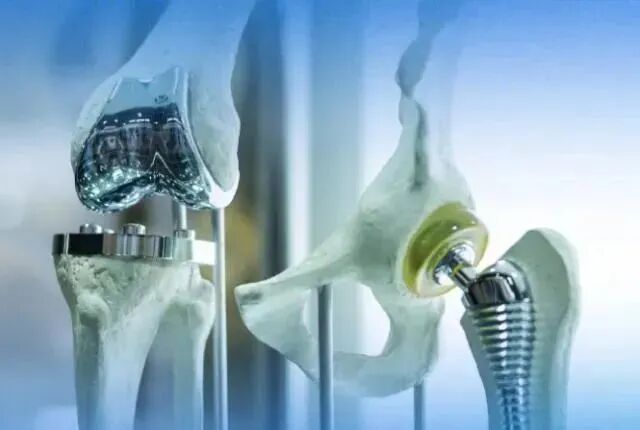

此次人工关节集中带量采购产品包括人工髋关节和人工膝关节,中选的髋关节平均价格从2.3万元下降至8000元左右,双膝关节平均价格从4.5万元下降至9000元左右,平均降幅达到80%。意味着骨科人工关节正式进入“千元时代”!

51岁杨某,以”左髋部疼痛伴活动受限多年”主诉入院。入院诊断:左侧股骨头坏死Ⅳ期;神经性皮。骨科鞠健主任团队为患者行左侧全髋关节置换术,其中骨科高值耗材费用从集采前的2.3万元左右,降到了集采后的8500元左右,大大减轻了患者经济负担。

59岁刘某,以”双膝关节疼痛伴活动受限3年”主诉入院。入院诊断:双膝骨性关节炎;骨质疏松症。骨科鞠主任为患者行双膝人工关节表面置换术,其中使用骨科高值耗材费用从集采前的4.5万元左右,降到了集采后的9300元左右,患者在来院之前了解到需花费近5万余元,如今使用国家集采后的耗材,让患者家属对国家骨科耗材集采的好政策赞叹不已。